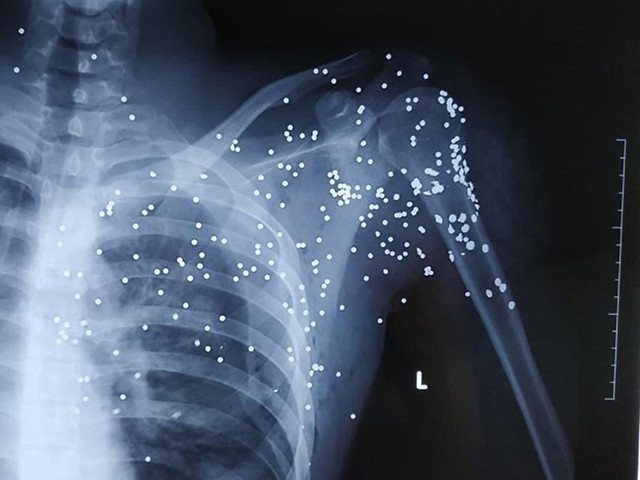

| Ảnh phim chụp trên người nạn nhân Hoàng cho thấy rõ nhiều vết đạn. (Ảnh bệnh viện cung cấp) |

Tiến hành sơ cứu và chụp chiếu, cơ quan y tế phát hiện vết đạn xuất hiện dày đặc nơi vùng phổi của anh Hoàng. Vì vậy, các bác sĩ đã phối hợp cùng gia đình chuyển nạn nhân lên cấp cứu tại Bệnh viện Hữu nghị Việt Đức (Hà Nội).

Theo anh Bùi Xuân Hải (anh trai Hoàng), do Hoàng bị nhiều mảnh đạn găm vào phổi và vào tim nên các bác sĩ tại Bệnh viện Hữu nghị Việt Đức chưa phẫu thuật. Hiện Hoàng vẫn đang trong tình trạng hôn mê, nằm tại phòng Hồi sức đợi các bác sĩ hội chuẩn và đưa ra giải pháp.